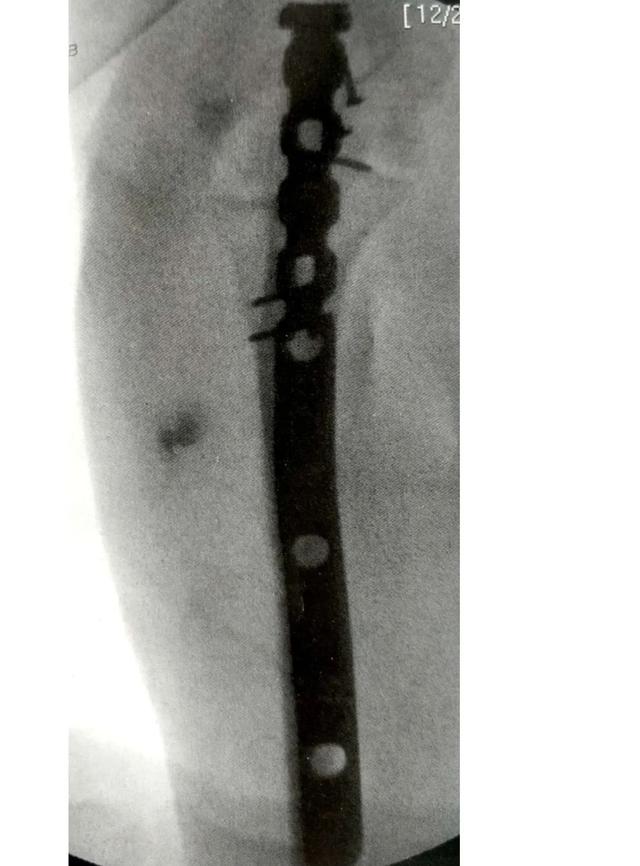

3.髓内钉固定

Rodriquez和 Eglseder描述了一种技术,髓内螺钉结合低切迹微型钢板周围固定。与那些报道使用3.5mm点接触动力加压钢板固定的结果相似。

Nijs等在21例患者中使用1枚鹰嘴截骨术的螺钉( OleON, Synthes, West Chester,PA)取得良好的效果。

Edwards等报道了使用一种多平面带锁髓内钉(OlecraNail,Mylad Orthopaedic Solutions,Mclean,VA)治疗鹰嘴近端骨折,包括复杂的不稳定类型。

尺骨鹰嘴骨折的正确处理方式及相关注意事项,需要的请收藏

A-B:肘关节骨折脱位

C-D:用多平面锁定髓内钉固定